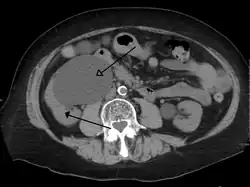

CT scan of bilateral hydronephrosis due to a bladder cancer

- Stone causing hydronephrosis[13]